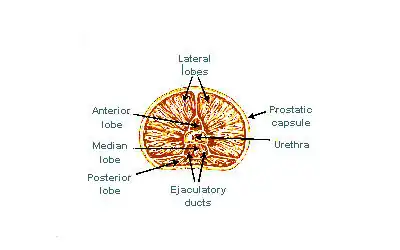

A estrutura interna da próstata foi descrita usando lóbulos e zonas.[4][1] Por causa da variação nas descrições e definições dos lóbulos, a classificação da zona é usada com maior predominância.[1] A próstata foi descrita como consistindo de três ou quatro zonas.[1][3] As zonas normalmente podem ser vistas em histologia, ou em imagiologia médica, como ultrassom ou IRM.[1][4] As zonas são:

| Nome | Fração da glândula adulta[1] | Descrição |

| Zona periférica (ZP) | 70% | Parte posterior da glândula que circunda a uretra distal e fica abaixo da cápsula. Cerca de 70–80% dos cânceres de próstata originam-se desta zona da glândula.[5][6] |

| Zona central (ZC) | 20% | Esta zona circunda os ductos ejaculatórios.[1] A zona central é responsável por cerca de 2,5% dos cânceres de próstata; esses cânceres tendem a ser mais agressivos e mais propensos a invadir as vesículas seminais.[7] |

| Zona de transição (ZT) | 5% | A zona de transição circunda a uretra proximal.[1] ~10–20% dos cânceres de próstata se originam nesta zona. É a região da próstata que cresce ao longo da vida e causa a doença de hiperplasia benigna da próstata.[5][6] |

| Zona fibromuscular anterior (ou estroma) | N/A | Esta área, nem sempre considerada uma zona,[3] é geralmente desprovido de componentes glandulares e composto apenas, como o nome sugere, de músculo e tecido fibroso.[1] |

A classificação de "lóbulo" descreve lóbulos que, embora originalmente definidos no feto, também são visíveis na anatomia macroscópica, incluindo dissecção e quando visualizados endoscopicamente.[4][3] Os cinco lóbulos são o anterior ou istmo, o posterior, os laterais direito e esquerdo e o médio ou mediano.[8]

Lóbulos da próstata

Lóbulos da próstata -